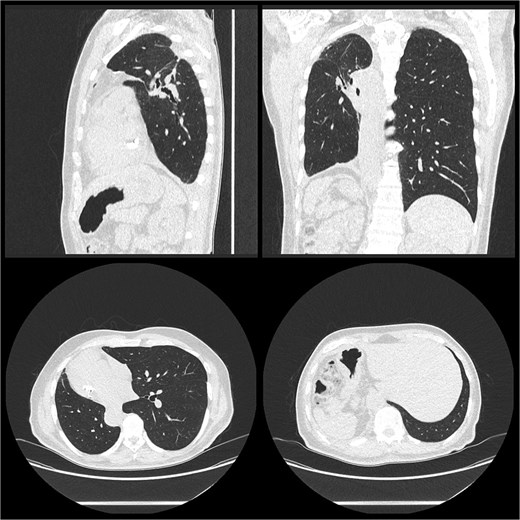

He was discharged post-operative Day 9. Histology confirmed moderately differentiated adenocarcinoma pT1cN0 in the right upper lobe and moderately differentiated adenocarcinoma pT1aN0 in the right lower lobe with clear margins for both. He was reviewed 2 weeks post-discharge and planned for surveillance with his respiratory physician (Fig. 2).